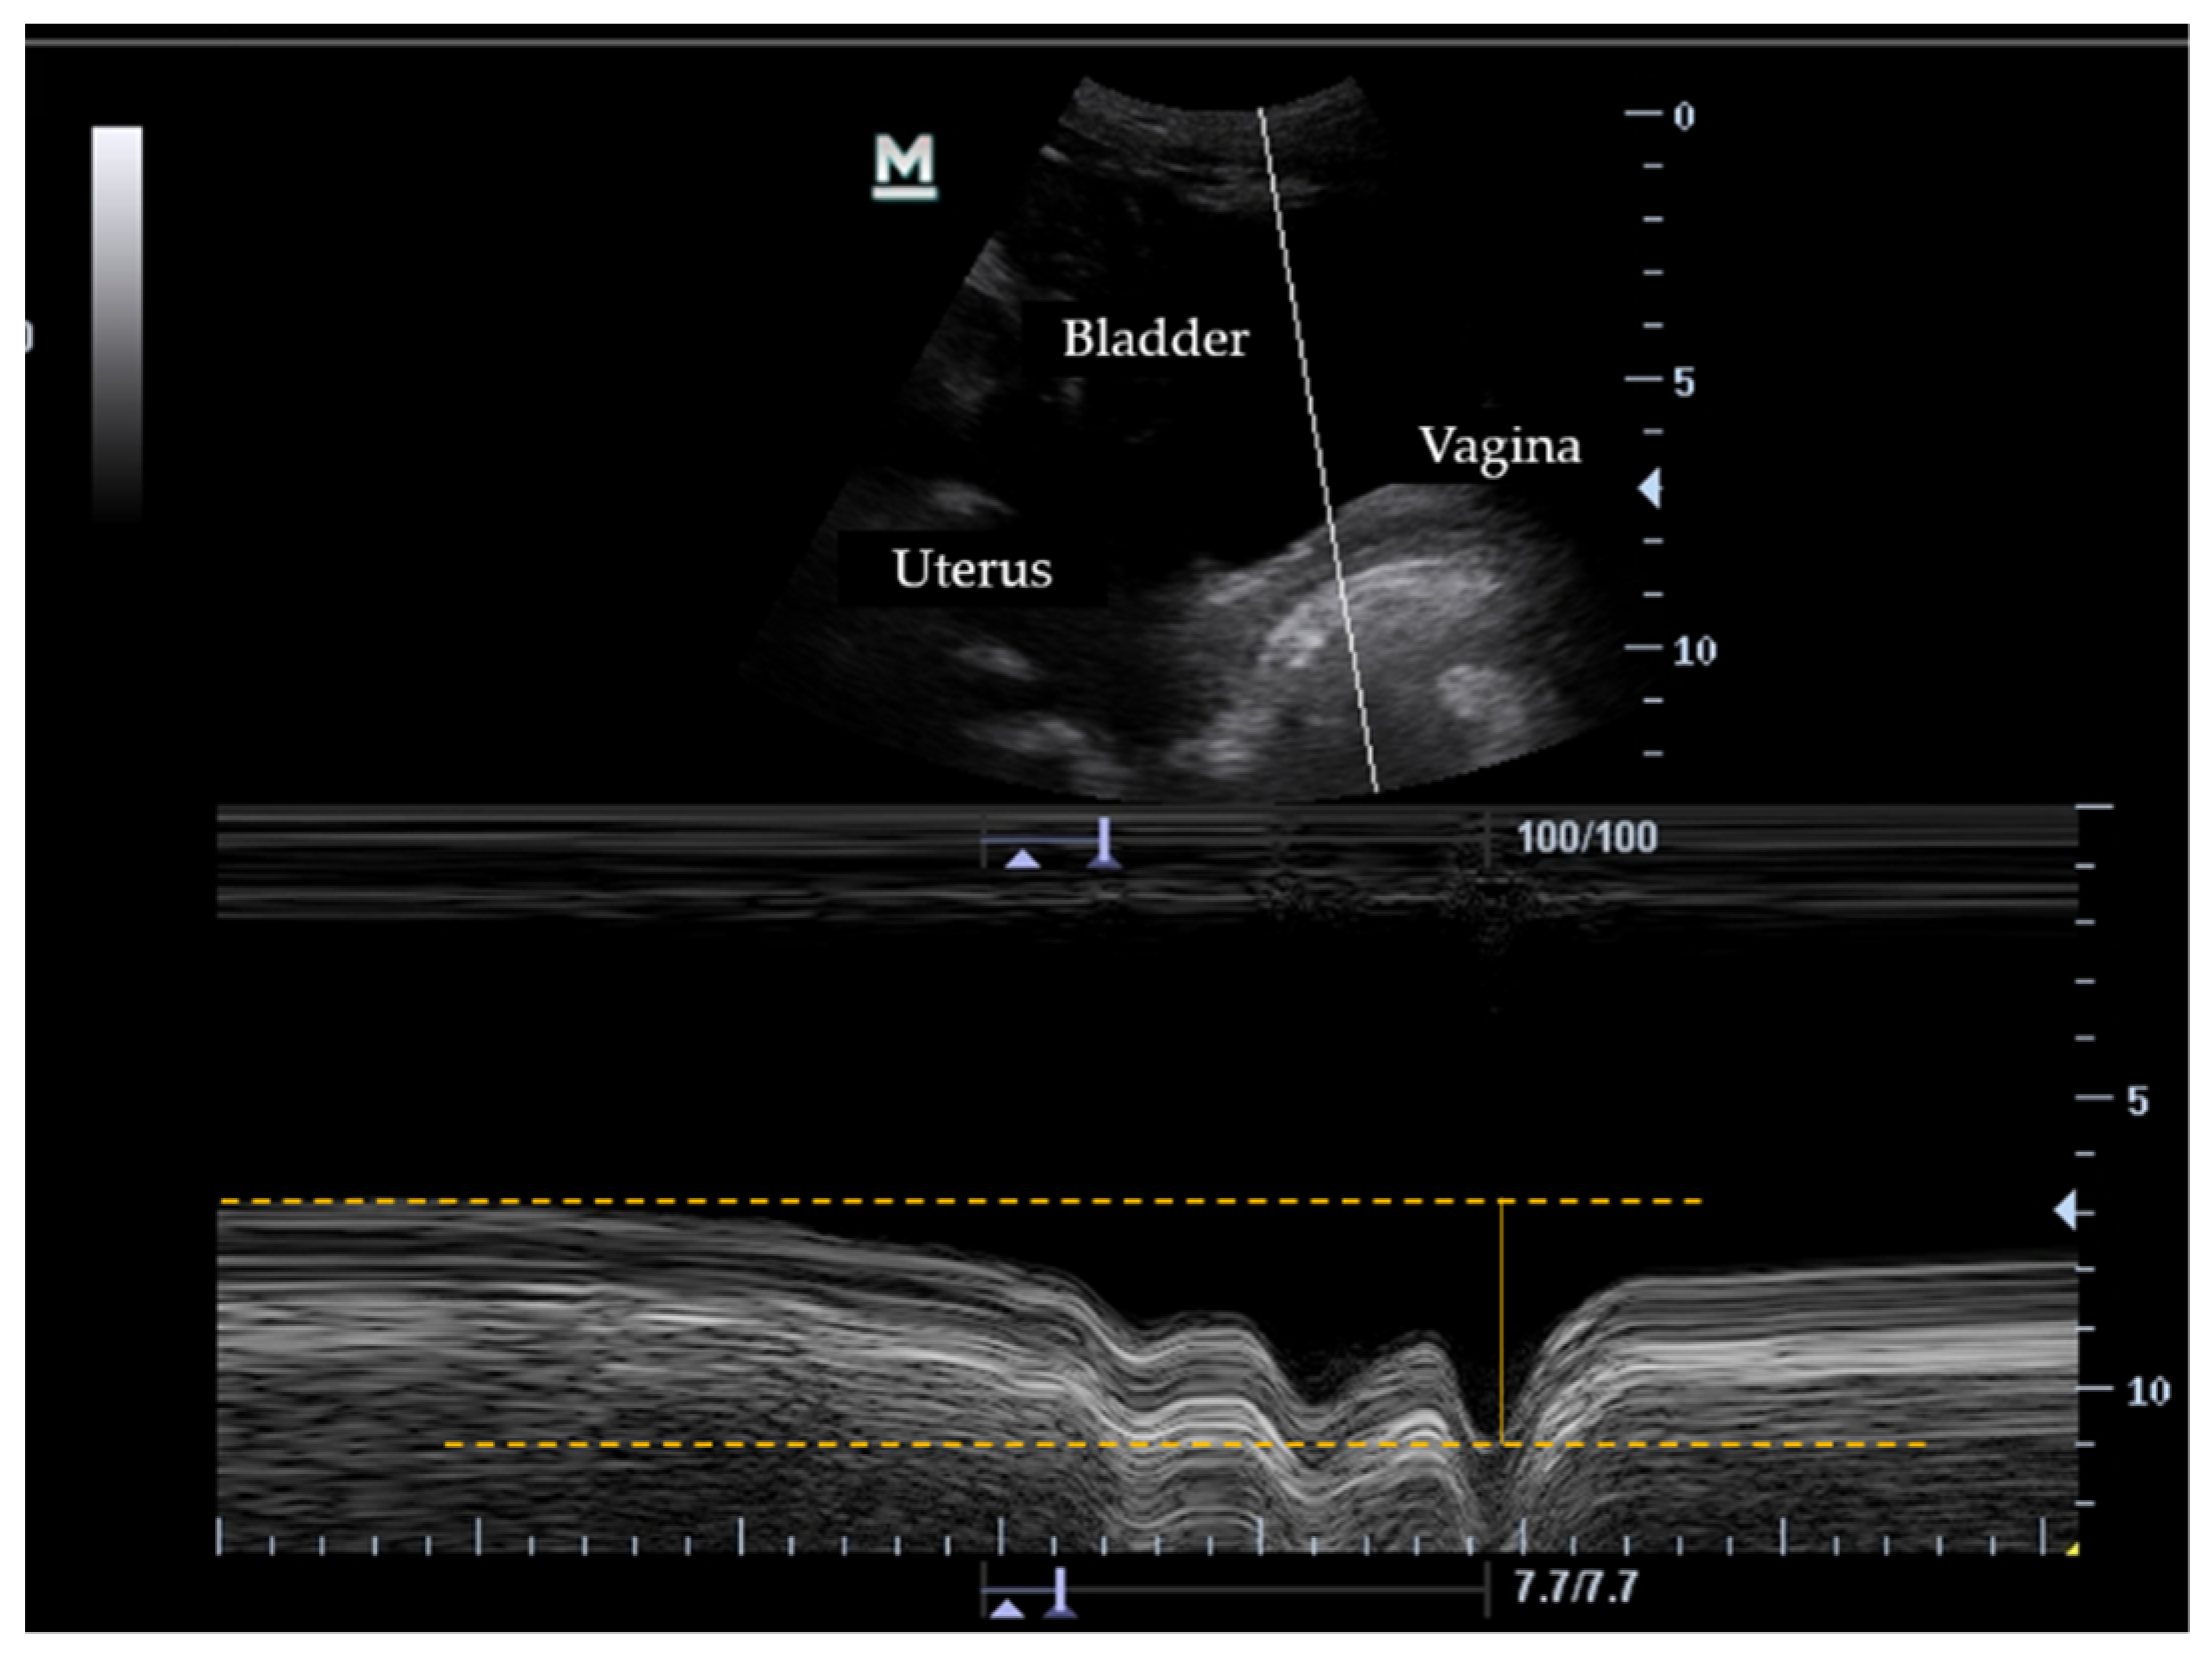

2.4. Data Collection